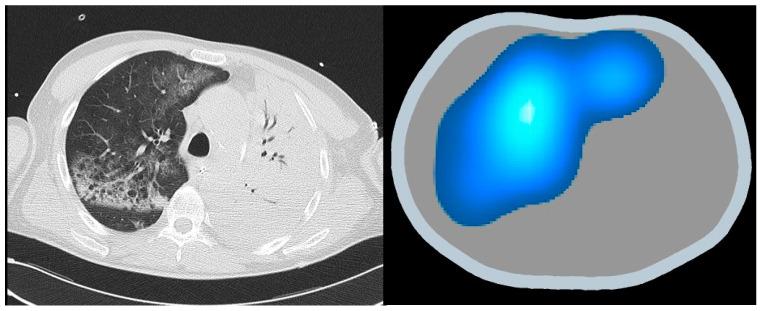

this narrative review explores the principles and applications of EIT, variable ventilation, and AI in critical care. EIT impedance sensing creates dynamic images of internal physiology, aiding the management of conditions like Acute Respiratory Distress Syndrome (ARDS). Variable ventilation mimics natural breathing variability to improve lung function and minimize ventilator-induced lung injury. AI enhances EIT through advanced image reconstruction techniques, neural networks, and digital twin technology, offering more accurate diagnostics and tailored therapeutic interventions.

本叙述性综述探讨了EIT、可变通气和AI在重症监护中的原理及应用。EIT阻抗传感可创建内部生理状况的动态图像,有助于管理急性呼吸窘迫综合征(ARDS)等病症。可变通气模拟自然呼吸变化以改善肺功能并将呼吸机诱发的肺损伤降至最低。AI通过先进的图像重建技术、神经网络和数字孪生技术增强EIT,提供更准确的诊断和量身定制的治疗干预措施。